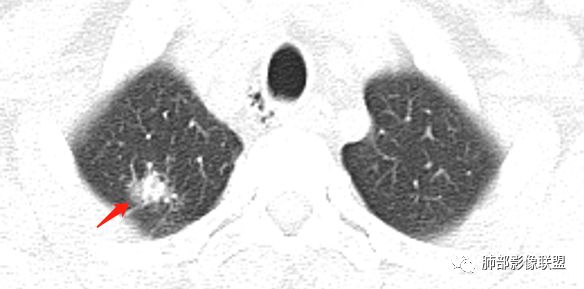

病史:男性,49岁,反复咳嗽月余,伴左胸痛;   影像:形态奇特,长毛刺,疑多灶,支气管阻塞不明显,毛刺不明显,纵膈窗密度不均,其内似见低密度,有凹陷,膨隆不除外,纵膈窗胸膜有点增厚。诊断:结核(右上肺)鉴别:不符合,无钙化,无胸腔积液;腺癌(无淋巴结)。处置:寻找结核相关检查,肿标,纤支镜,增强。

患者中年男性,主诉:咳嗽  胸痛。  胸CT:右肺上叶尖段占位,病灶位于支气管外,病灶周围部分区域可见毛玻璃影,病灶边缘不规则,部分区域可见平直,胸膜牵拉(无胸膜凹陷),柔软长毛刺,分叶,纵隔窗病灶没可见低密度区,左肺尖可见一点状病灶,病灶整体考虑良性疾病:感染性病变(结核?),感染后机化?。恶性病变待除外。

右肺上叶结节,边缘平直为主,病灶比较散,周周似乎有卫星病灶,边缘有胸膜牵拉,从粗到细,左肺尖奕有卫星灶,综合考虑结核。

晨读:患者中年男性,反复咳嗽1月余,伴左胸部疼痛1周就诊。胸部CT:右肺上叶尖后段不规则结节,见长毛刺、胸膜牵拉、条索影,周围见卫星灶。未见明显淋巴结肿大,符合结核病变。鉴别其他。但其病灶位于右肺,主诉左胸痛,是误写,还是?

一米阳光:    晨读,右上肺结节影,形态不规则,边缘平直,部分凹陷,长软毛刺,胸膜牵拉,周围卫星灶。考虑结核。鉴别腺癌,部分边缘彭隆

傅昌瑜:  男,49岁,反复咳嗽1月余,伴左侧胸痛1周。右肺上叶尖段结节,边缘平直、凹陷,周周似乎有卫星病灶,边缘有胸膜牵拉,从粗到细,左肺尖见小点状病灶,考虑良性病变,结核可能性大。

小飞:  晨读:右肺上叶不规则结节灶,沿支气管走形分布,边缘平直,U型凹陷,脊柱侧有少许磨玻璃影,左肺尖少许斑点灶,综合考虑结核。

南边:这病史,慢性或亚急性炎症,癌都可以

影像,气管憩室,两肺尖都有病灶,长索条

右肺上叶病灶两部分

纵隔窗提示内侧部分密度不够实

边缘平直、凹陷为主,部分膨隆

内部小点状影提示可能支气管腔内粘液栓

左肺尖及右肺病灶附近见小斑点,边界尚清

1、病灶整体形态不是类圆形,边缘凹陷、平直为主,长轴重建可能更明显,长索条,附近卫星灶,左肺尖有类似小高密度影;按常规:首先要考虑结核

结果:结核合并真菌(曲霉菌)感染